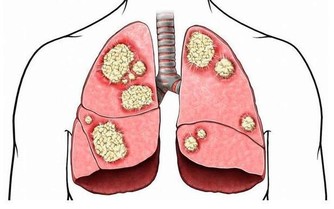

肺癌是中國發病率最高的癌症,也是死亡率最高的癌症。不管是何種癌症,我們都知道,一般發現時都是晚期,很難治愈。如果癌症早期能夠及時發現,經過治療後的五年生存率會大大提升。對於患者來說疾病的早發現要比“靈丹妙藥”見效好!

在德克薩斯州旅行結束後,Bill決定要仔細檢查一下自己的肺,畢竟他是一位有著55年菸齡的老煙民。在找到梅奧診所健康系統肺科的Adel Zurob醫生,醫生了解情況後建議Bill做一項肺癌篩查(低劑量CT)。檢查結果顯示:右肺有一個小的癌變結節。通過進一步的正電子發射斷層掃描(PEC-CT),顯示肺部以外沒有擴散或轉移的徵象。醫生建議,立即進行手術治療。

在醫生切除了Bill的癌變病灶後,還為他進行了胸部檢查以確定是否有淋巴結轉移的跡象,並對可疑的淋巴結進行了預防性切除。Zurob醫生說:“Bill的肺癌治癒的可能性極高,對Bill來講,沒有出現任何轉移是再好不過的了。”

梅奧診所近期公佈一項實驗調查,他們對梅奧診所的53000名)每年接受低劑量CT掃描或標準胸部X線檢查患者(均為重毒吸煙患者進行分析,結果顯示,接受CT掃描的患者比接受胸部X光檢查的患者肺癌死亡風險降低了20%。

Zurob醫生說:“如果肺癌早期篩查能夠用於每個菸齡30包年的患者,那麼每年我們可以避免2萬人的死亡,據“疾病預防控制中心”報導,美國每年有157,000人死於肺癌。這比任何其他類型的癌症都多”。